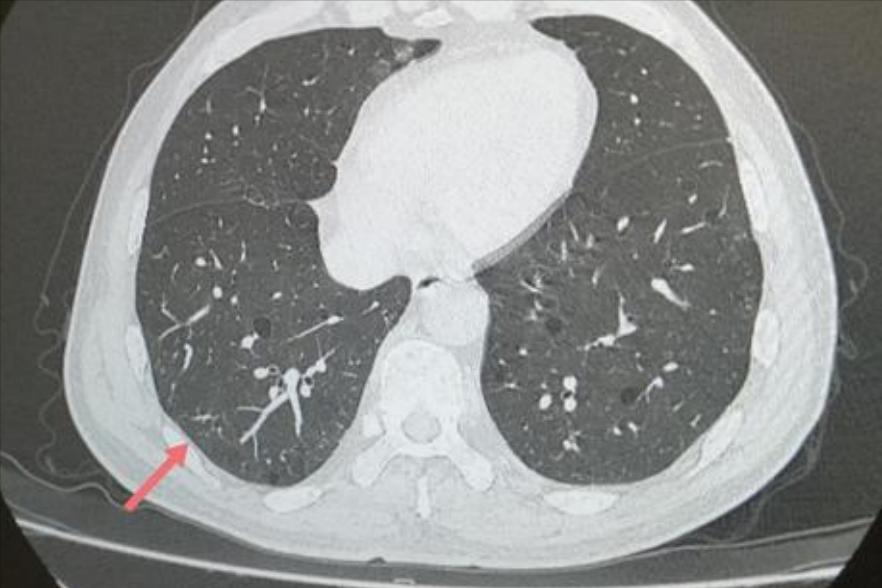

主任好:这是我第四次给您发帖,第三次帖您回复我是“……这个新报的6mm结节,就是前面那个空泡结节变的。既然有明显变化,那就没事了。脱恐。继续我的医嘱,半年后复查,希望全消。”这次复查报告的结果没有全消,但明显变小、变淡,这次报告说与上次比较明显吸收,考虑炎性可能性大。

下面是这次检查的CT报告和图片(这次医院不给刻光盘了,在门诊医生电脑上拍照的)。

报告说:结节较前基本吸收。您不能太贪心,这么大的空泡结节,您不能要求消失得一点点渣渣都不能留吧?